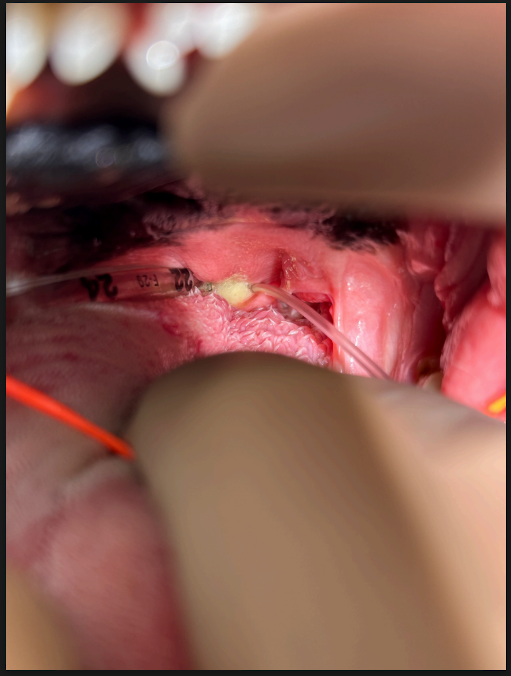

▼軟口蓋手術前:軟口蓋過長(術前)